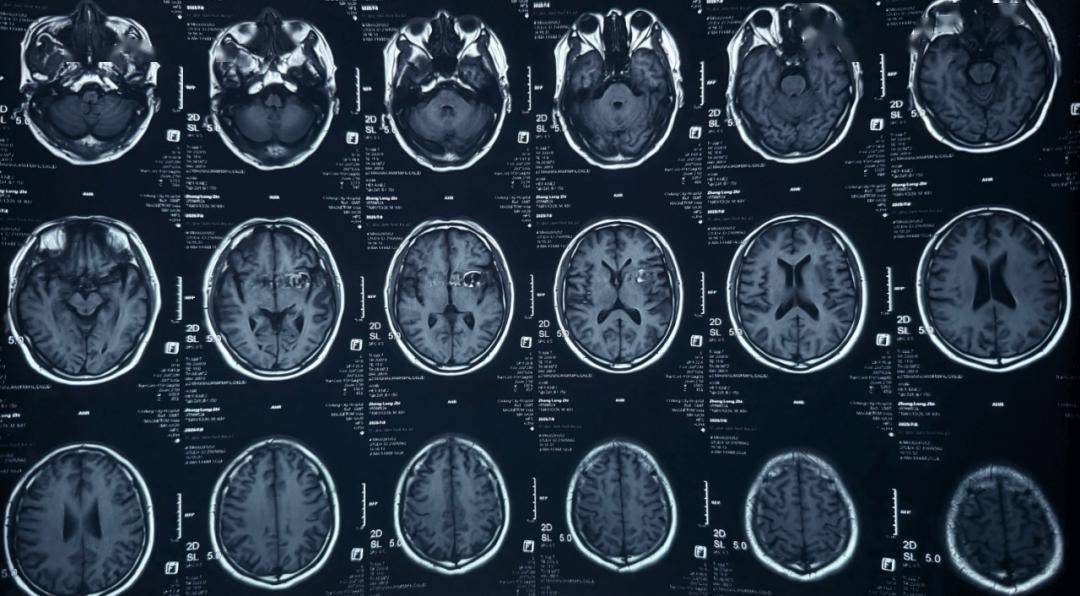

术前影像

术前正位DSA

术前侧位DSA

术前CT